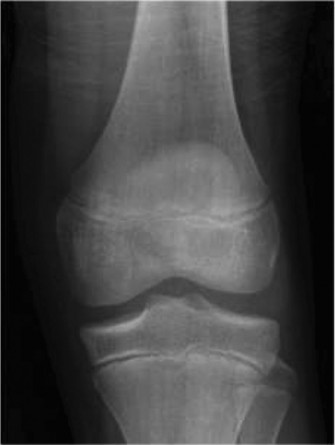

The risk of graft failure observed in pediatric patients with allograft reconstruction? CASE 17 A 10-year-old female soccer player presents to the sports clinic with a several month history of knee pain and swelling along the lateral joint line. The patient notes pain and a snapping sensation laterally. She also describes occasional mechanical symptoms as well. On physical exam she is unable to fully extend the knee. The patient otherwise has a stable ligamentous examination of the knee. Radiographs are obtained and shown in Figure 10–29.

Figure 10–29

The correct answer is (B). The patient’s clinical examination is concerning for meniscal injury (lateral joint line pain) with the snapping sensation concerning for an unstable meniscus. The radiographs demonstrate lateral joint space widening, cupping of the lateral tibial plateau, and a hypoplastic lateral tibial spine—all suggestive of a discoid meniscus. Discoid menisci are classified using the Watanabe classification as complete, incomplete, or Wrisberg (lack of posterior meniscotibial attachment to the tibia). Unstable variants create the classic “snapping” sensation. The diagnosis of a discoid meniscus can be made with three or more 5-mm sagittal images with meniscal continuity. As the patient has had several months of pain with